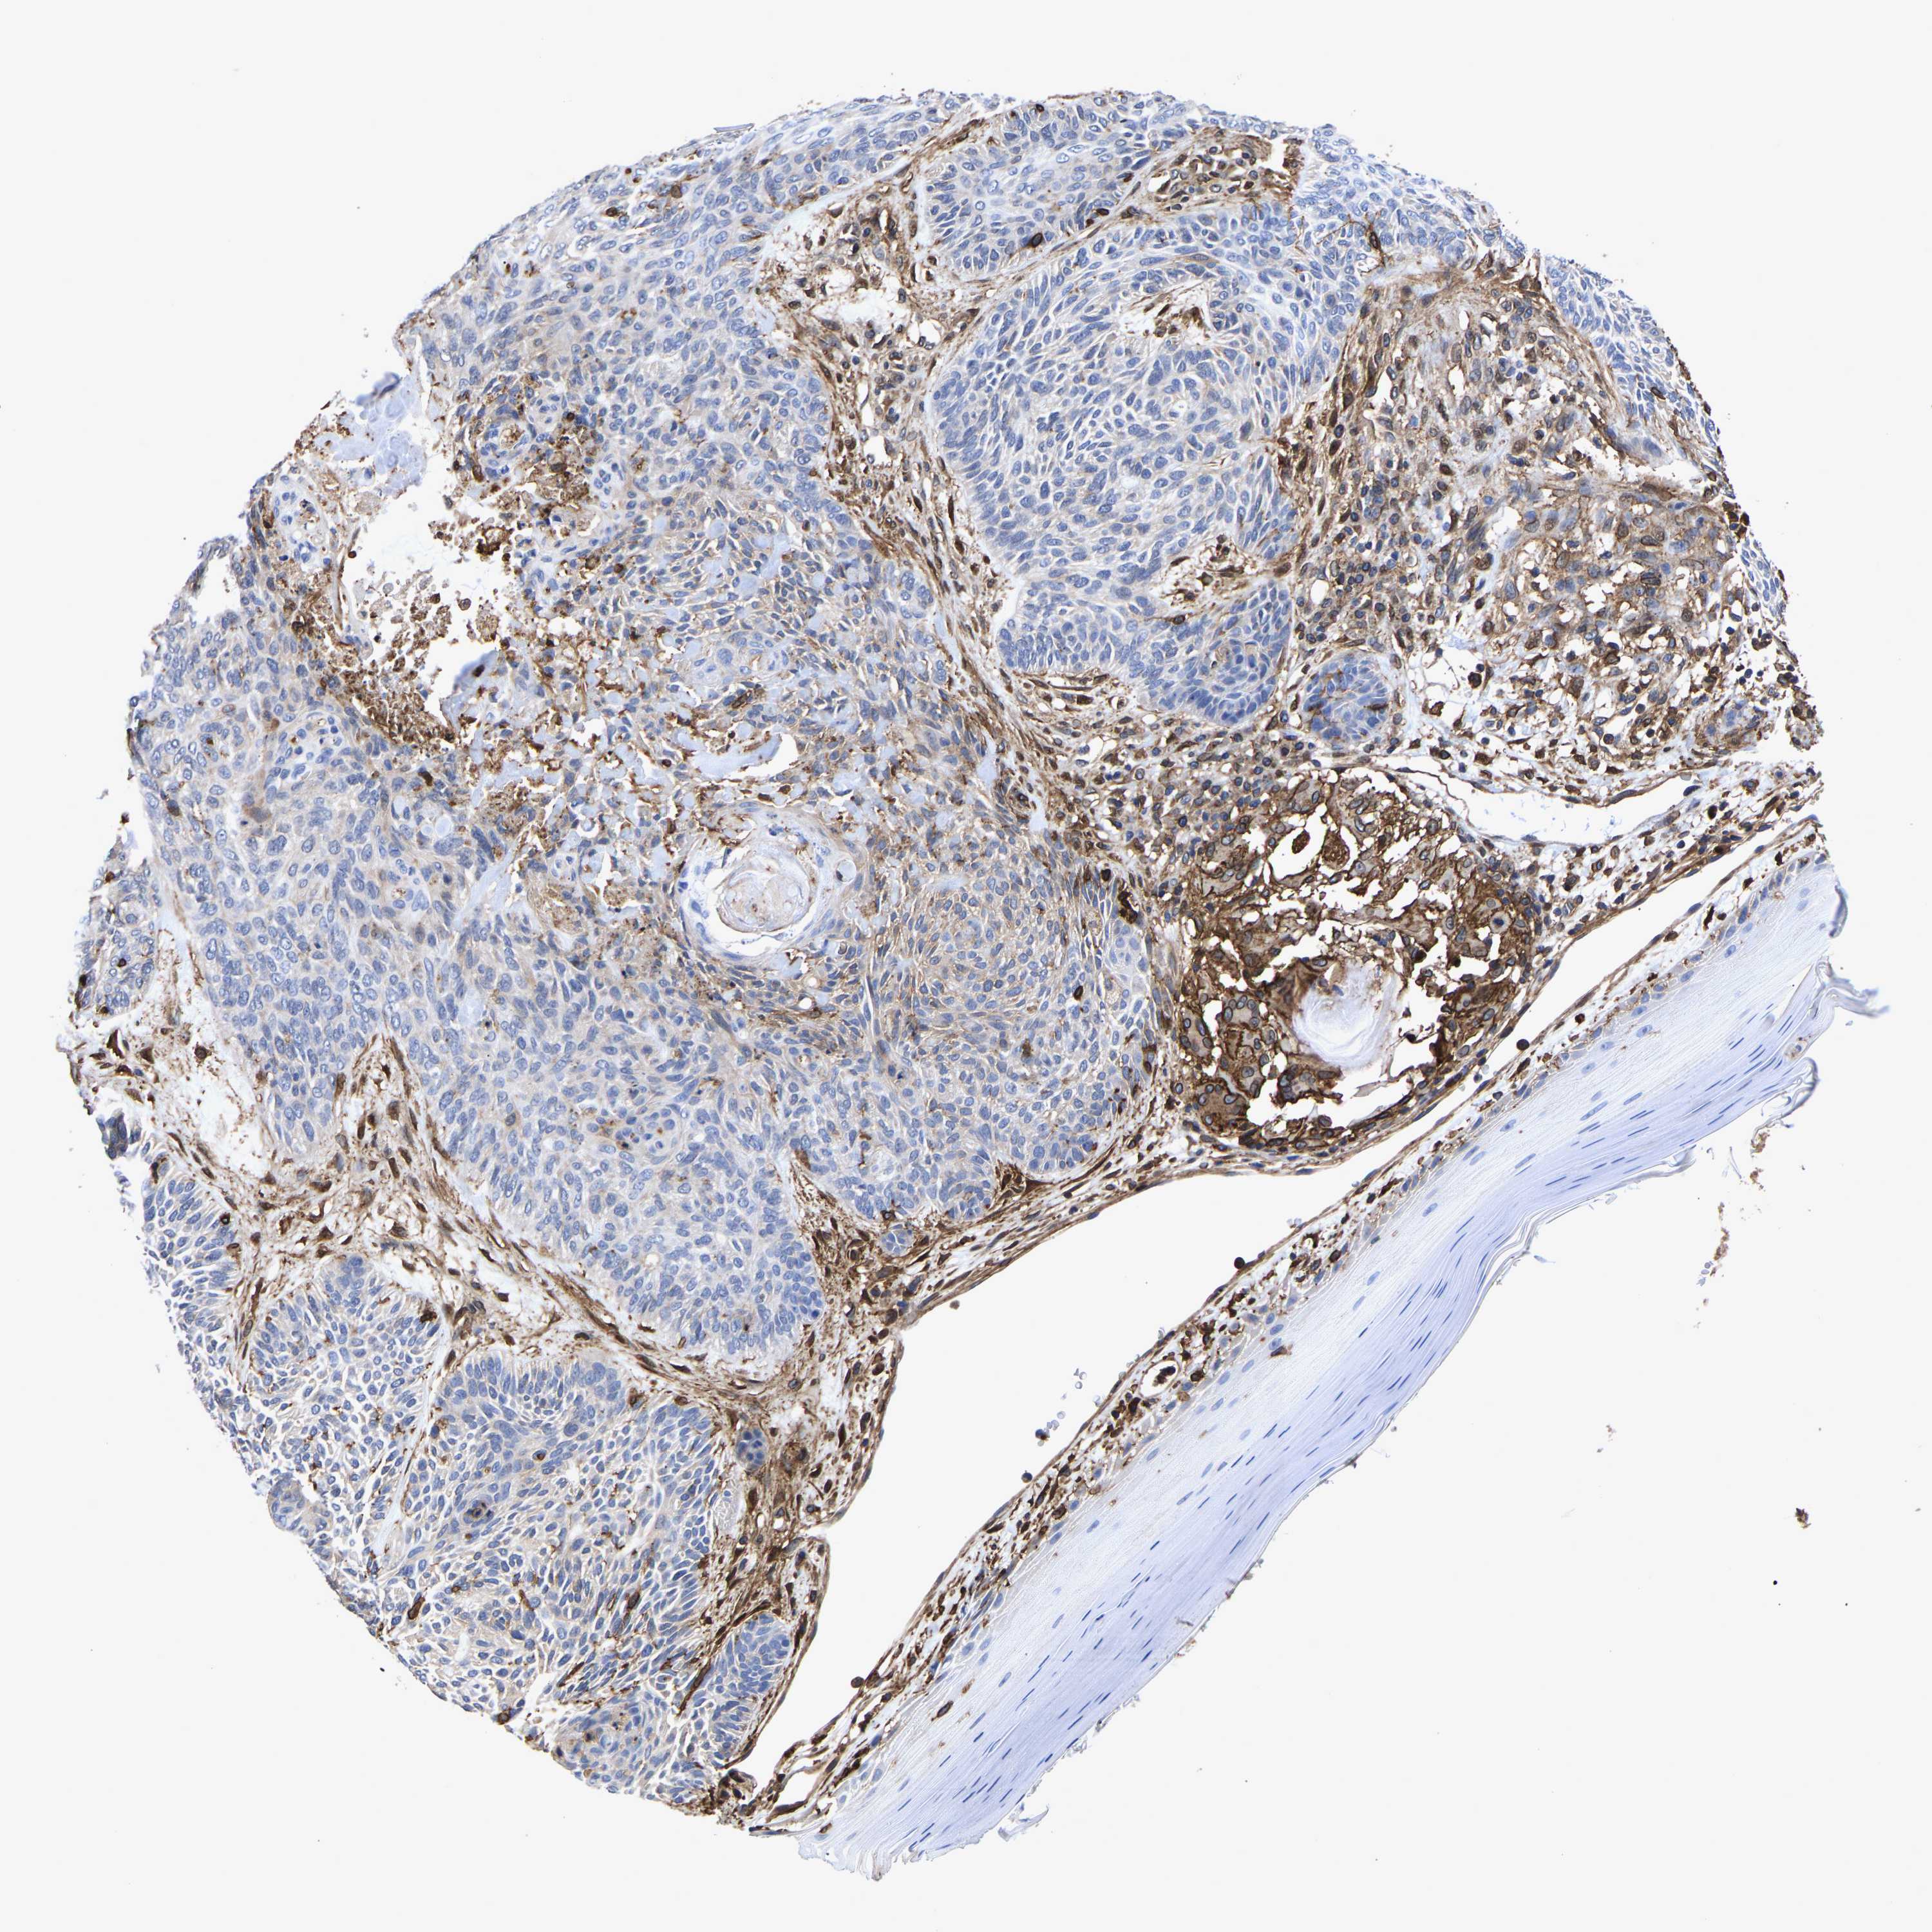

Basal cell and squamous cell cancer

SKIN CANCER - Protein expressioni

A mouse-over function shows sample information and annotation data. Click on an image to view it in a full screen mode. Samples can be filtered based on level of antibody staining by selecting one or several of the following categories: high, medium, low and not detected. The assay and annotation is described here.

Antibody stainingi

Antibody staining in the annotated cell types in the current human tissue is reported as not detected, low, medium, or high, based on conventional immunohistochemistry profiling in selected tissues. This score is based on the combination of the staining intensity and fraction of stained cells.

Each image is clickable and will lead to virtual microscopy that enables deeper exploration of all samples and also displays staining intensity scores, fraction scores and subcellular localization as well as patient and tissue information for each sample.

Antibody HPA018844

Staining

High

Intensity

Strong

Quantity

>75%

Location

Nuclear

Squamous cell carcinoma, NOS